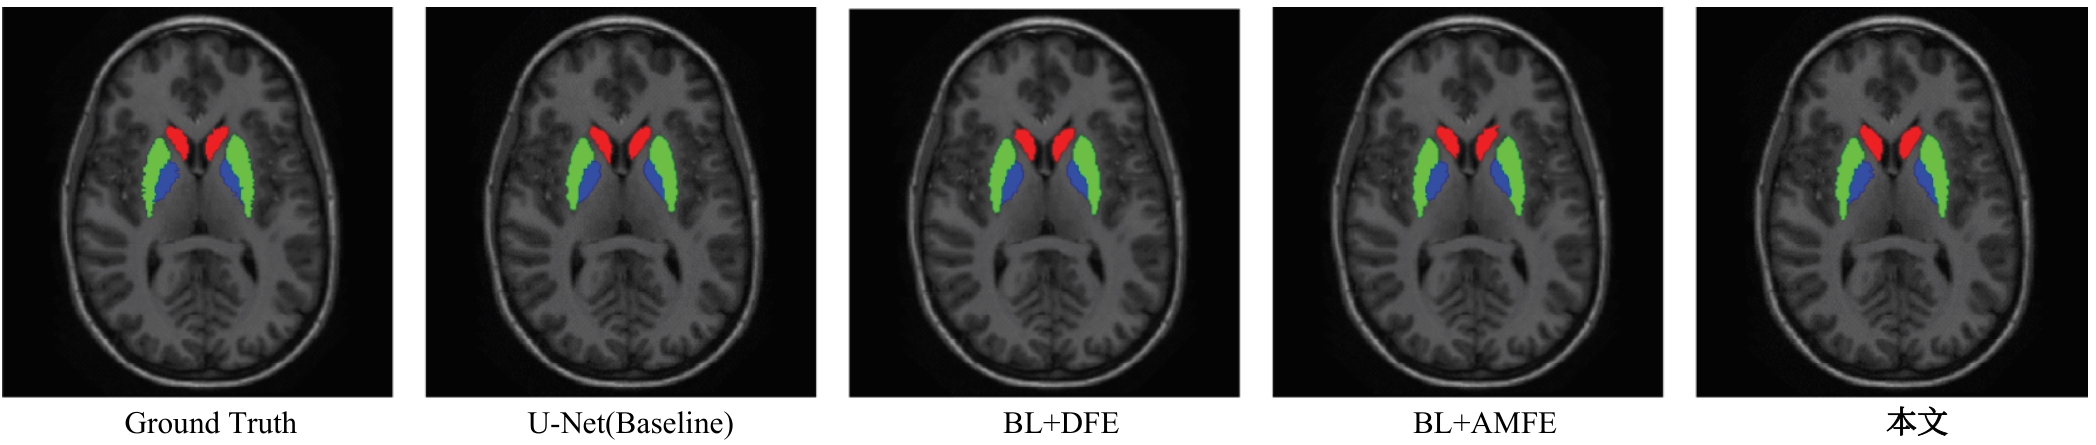

针对脑皮层下组织部分结构(如纹状体)在医学影像中目标小、对比度低,图像分割难度大,在自动医学诊断中应用比较困难的问题,本文基于深度学习的方法提出了一种医学图像分割网络,在磁共振成像中分割组成纹状体的苍白球、尾状核、壳核3部分。本文提出的网络模型具有捕获全局和局部特征的能力,并建立了全局与局部信息的相关性,在深度不退化的同时有效融合不同尺度的深层语义特征和浅层细节特征,实现对纹状体的精确分割。模型在公开的脑部数据集上进行了验证,并与其他先进的方法进行对比,结果表明本文的戴斯相似系数、平均交并比、95%豪斯多夫距离分别为94.26%、90.94%、3.82,均优于其他几种方法,达到了先进水平,这表明本文模型可以提高对纹状体的分割精度,为相关疾病的研究提供依据。